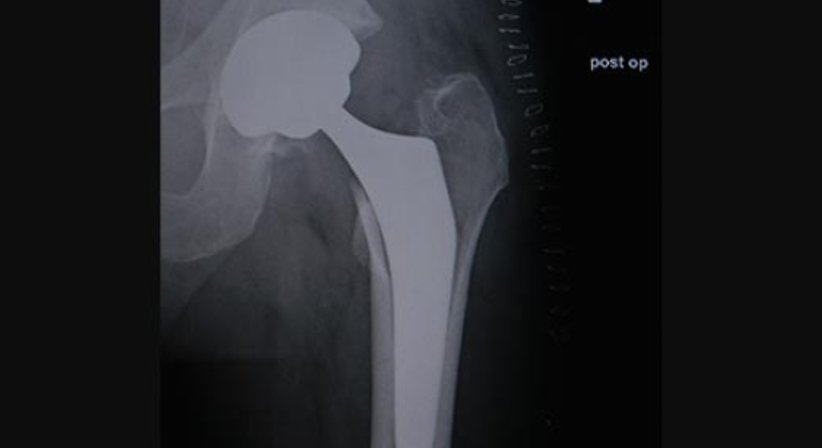

Jeder Operation geht eine digitale Planung voraus. Dabei werden die ideale Größe, Ausrichtung und Position der Hüftprothese bestimmt. Die Hüftendoprothese, die aus mehreren Komponenten besteht, ersetzt die Verbindung zwischen dem Oberschenkel- und Beckenknochen.

Ich operiere nach der minimal-invasiven, muskelschonenden (die Muskeln werden weder durchtrennt, noch abgelöst) AMIS Methode, die eine schnelle Heilung und rasche Genesung ermöglicht. Bei dieser Operationstechnik ist der Zugang zum Hüftgelenk von vorne. Dadurch kann das künstliche Hüftgelenk, die Hüftprothese, besonders behutsam eingesetzt werden. Die Prothese wird zementfrei implantiert, wobei der Knochen an die Implantatoberfläche aus Titan anwächst. Die Patienten können sich in der Regel einen Tag nach der Operation weitgehend schmerzfrei bewegen. Der Krankenhausaufenthalt dauert meist nicht länger als fünf bis sieben Tage.